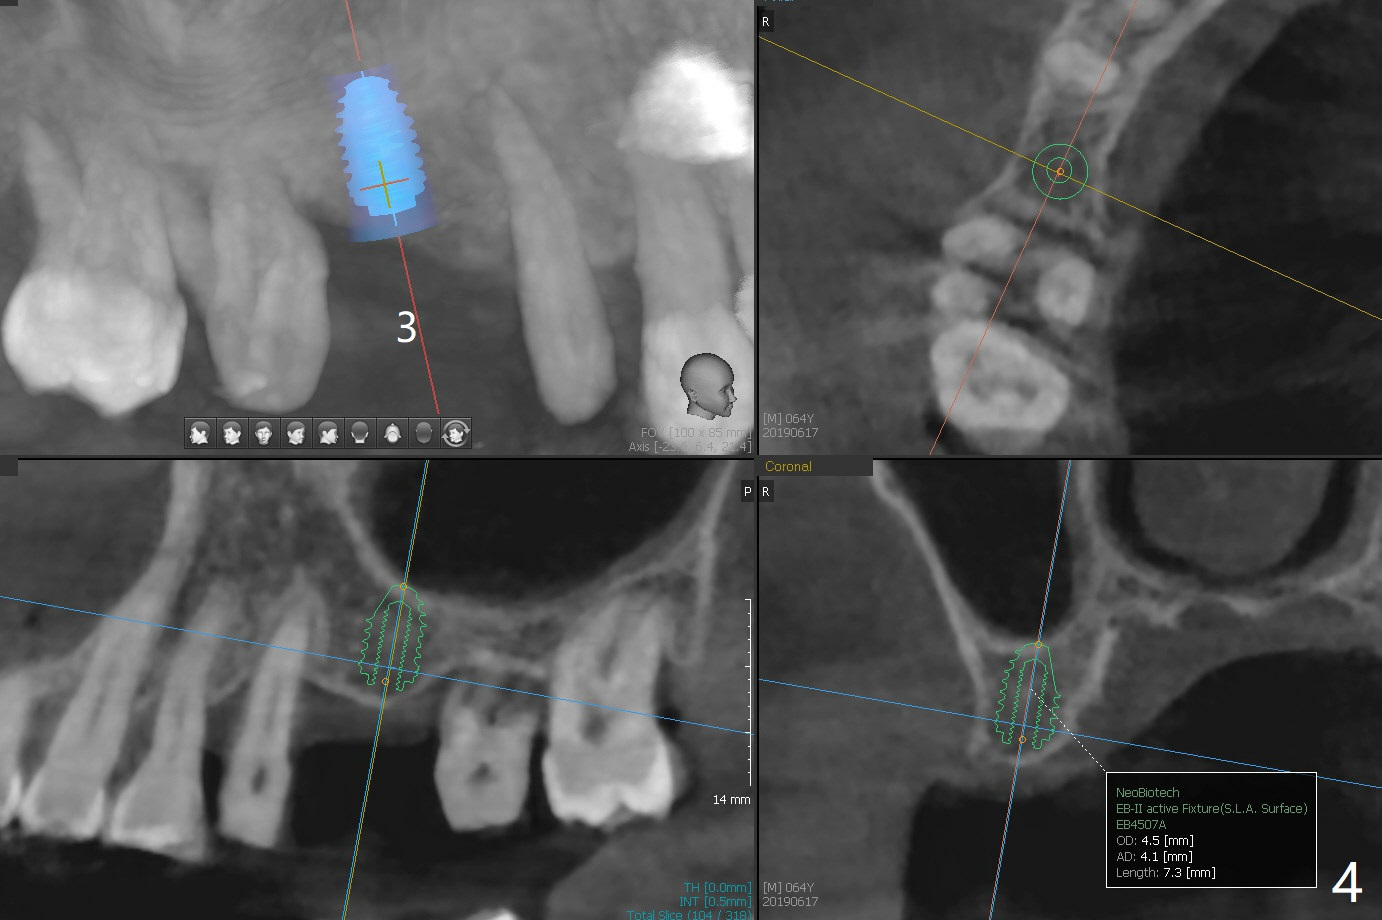

A 64-year-old man has a loose FPD at #2-4. After discussion, he agrees to have it removed for implant at #3 (Fig.1). In fact the bone loss at #2 is severe (Fig.2, as compared to #4 (Fig.3)). When the implant osteointegrates (Fig.4), make single unit crowns and let the patient decide whether the tooth #2 is salvageable or not.